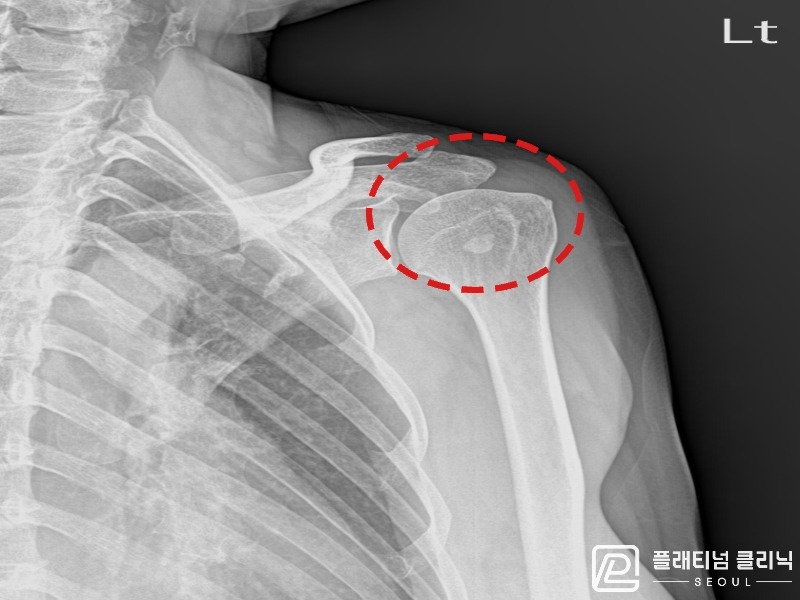

[촬영시기:21.10.21~21.10.29]

[석회분쇄흡입술] 좌측 어깨의 극심한 통증으로 팔을 어깨 이상으로 들기도 어려웠던 60대 여성 환자로, X-ray에서 극상근건 내 대량의 석회 침착이 확인되어 석회분쇄흡입술을 시행하였습니다.